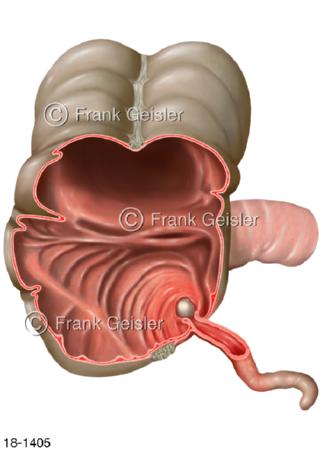

18-1405 Entzündung Darm, Blinddarm mit Appendizitis